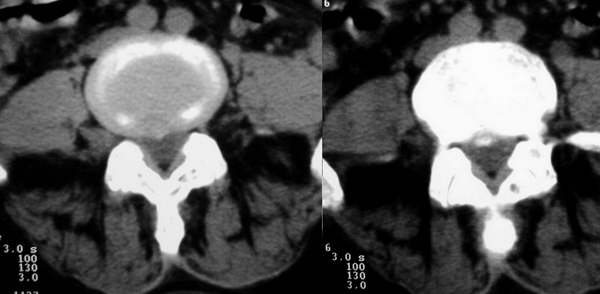

标题: CT3877:神经纤维瘤 [打印本页]

标题: CT3877:神经纤维瘤

女:67岁,右下肢疼痛20余年。

行腰椎间盘扫描。

右侧神经源性肿瘤,是神经纤维瘤还是鞘瘤不敢说,不过神经鞘瘤较多见吧。

还有一种可能也要想到:神经根鞘囊肿,也有的叫囊性神经根。

mr在此可能要明显的优于ct;

此患者外院手术病理为:神经纤维瘤。在外院做mri平扫+增强,至今没照到mri图像感到遗憾。如果什么时间借到片子一定照下来传给大家。